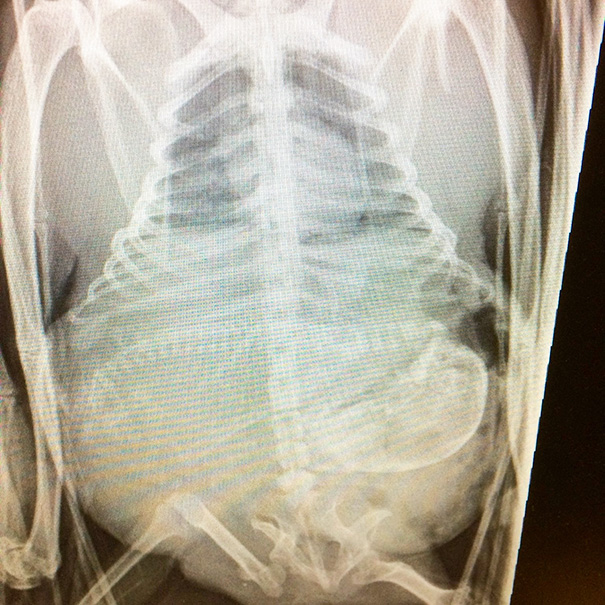

X-Ray Of Pregnant Bat

Why is it on one side. I'm not sure but it looks like it's bulging out the right not front.

This is normal. Any woman who has been pregnant can attest that sometimes the baby (or babies) will lay on one side. Can look pretty funny too! Have to remember there's also a lot of amniotic fluid around the baby which fills up the space so while it may look like the baby is smack in the middle it's often not.

Pregnant Bat's X-Ray

X-Ray Of A Pregnant Bat